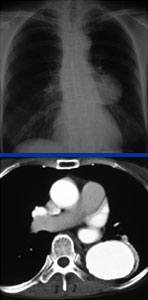

症例2

67歳 男性

【主 訴】

検診異常

【起始・経過】

平成18年5月検診にて胸部大動脈瘤を指摘。

7月当院紹介受診。

【既往歴】

65歳 胃癌 → EMR

高血圧(+) 糖尿病(−) 喫煙歴(−)

【治療計画】

Gore社TAG stent留置術

胸部CT検査

腹部CTA検査